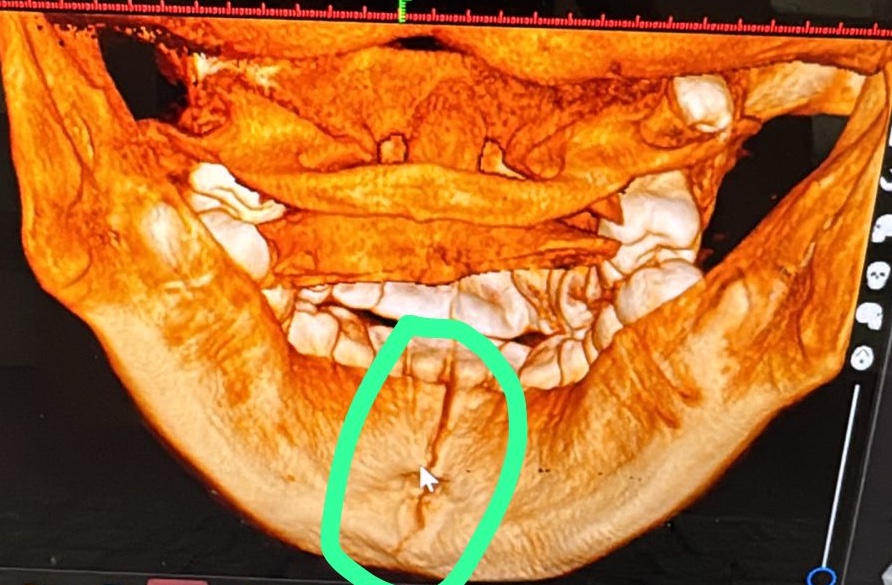

El padre Noel Ulloa, indico que su hija tiene la mandíbula rota, que requiere una cirugía y que ellos no cuentan con los recursos para costear los gastos.